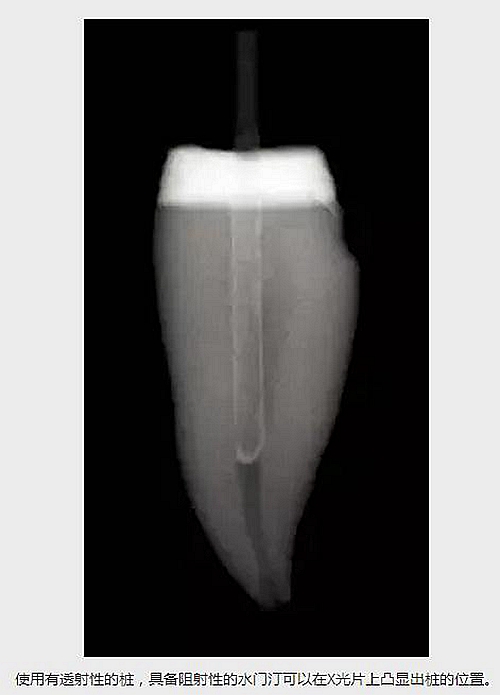

水門(mén)汀的阻射性,比如Multilink Automix (Ivoclar /Vivadent)或者使用其他水門(mén)汀。如果使用了一個(gè)有透射性的樁,有阻射性的水門(mén)汀可以在X光片上凸顯出樁的外形。 (見(jiàn)下圖)

使用有透射性的樁,具備阻射性的水門(mén)汀可以在X光片上凸顯出樁的位置。